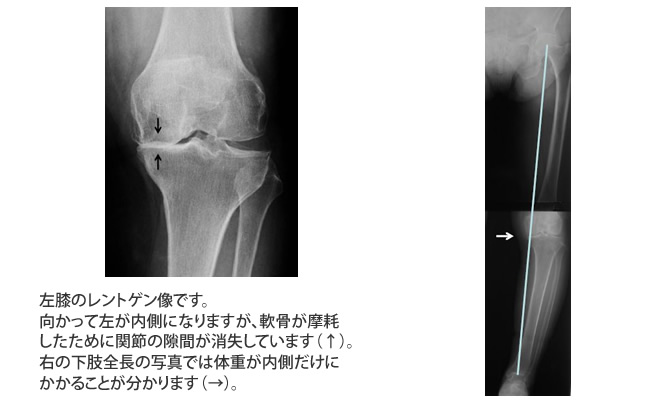

左のレントゲン写真をご覧ください。O脚変形により体重が膝の内側のみにかかっていた状態が、手術後には膝の真ん中にかかるようになっています。

このように手術は脚の変形を矯正するとともに痛みをとり、日常生活動作を容易にさせることができます。